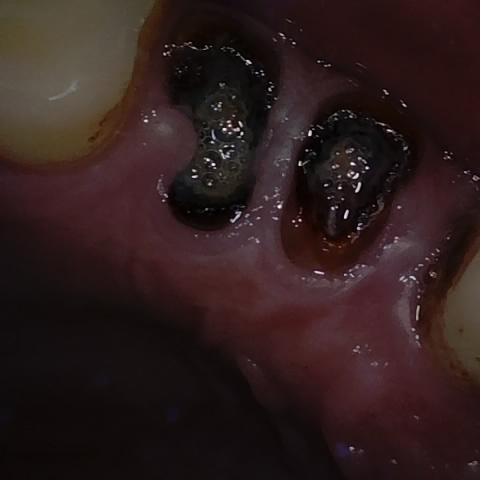

Image 1230 / 1743

NHD36692

Annotated as "Good"

Original Image Rendering Image